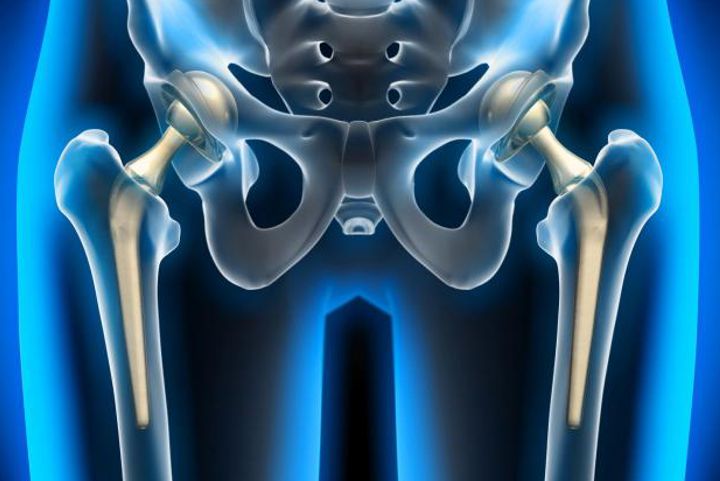

Kalça ekleminin normalden dışarıya çıkması durumudur. Kalça çıkığı, doğuştan olabileceği gibi, bir travma sonucu da meydana gelebilir. Kalça, femur adı verilen uyluk kemiği ile pelvisin birleştiği bir eklem olup, vücudun en büyük eklemidir. Normalde femur başı, pelvisteki asetabulum adı verilen bir çukura oturur. Kalça çıkığında ise femur başı bu çukura oturamaz ve eklem dışına çıkar. Kalça çıkığı, erken müdahale edilmediği takdirde ciddi sağlık sorunlarına yol açabilir.

Ayrıca, kalça eklemindeki yumuşak doku hasarları onarılabilir. Tedavi sürecinin ardından hastaların eklem hareketliliğini tekrar kazanabilmesi için fiziksel terapi önemlidir. Terapi, kasları güçlendirir ve eklemdeki sertliği giderir. Özellikle yaşlı hastalarda, kalça eklemi tamamen hasar görmüşse ve cerrahi tedaviyle düzeltilmesi mümkün olmuyorsa, kalça protezi takılabilir. Kalça protezleri, eklemdeki ağrıyı azaltır ve hareket kabiliyetini artırır.